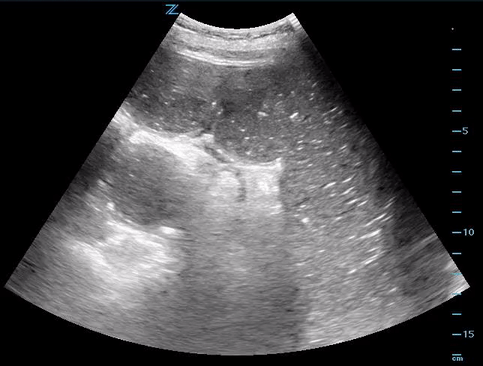

Why does our patient have elevated LFTs?

As the bowel becomes more distended it can cause obstructions in other parts of the abdomen (billiary system, kidneys, etc) as shown in the images below.

CT scan confirmed SBO secondary to incarcerated loop of small bowel within R obturator hernia with moderate right sided hydronephrosis.